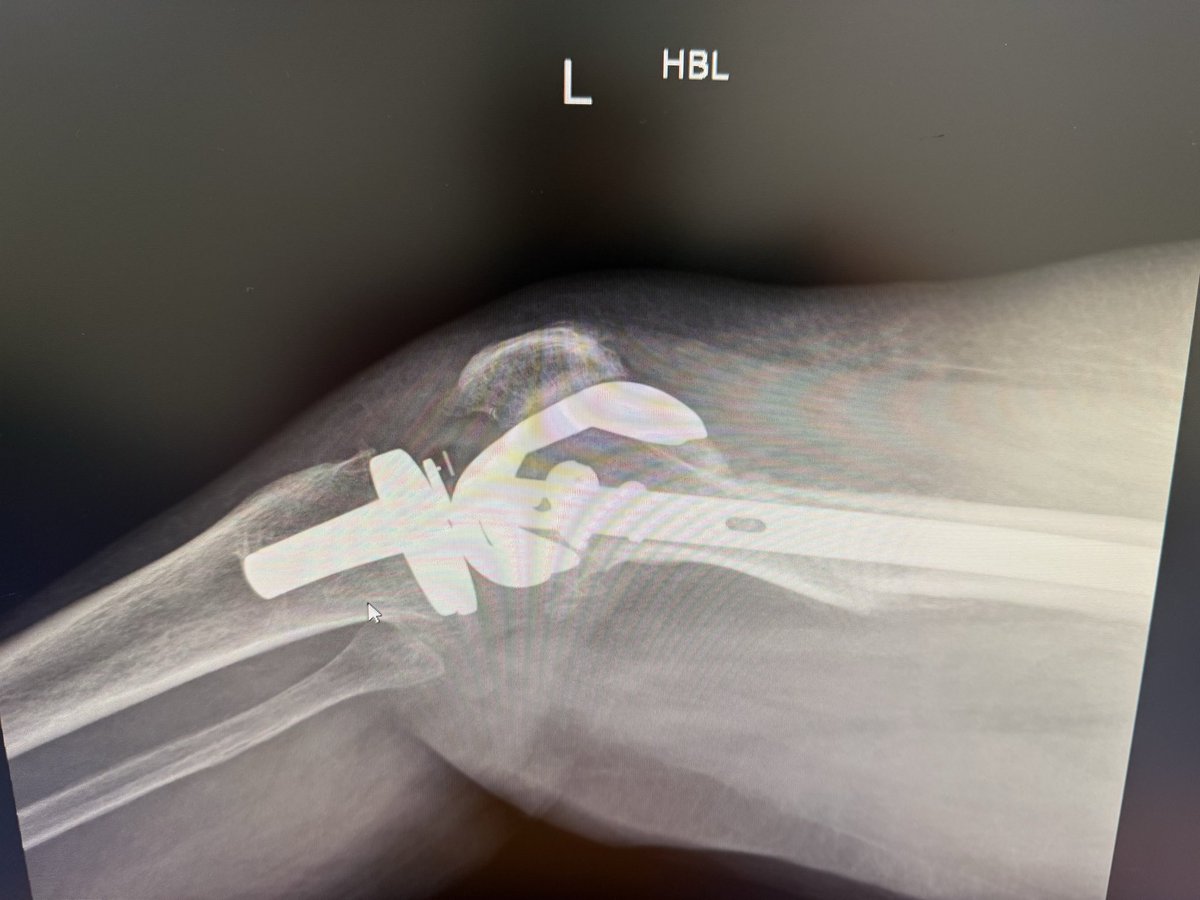

Can you answer our free question of the day? A patient presents to the trauma bay after involvement in a motor vehicle collision. Radiographs obtained in the trauma bay demonstrate a right distal femur fracture, as seen in Figure A. In surgery, the articular block is reduced, and reduction is held with headless compression screws. A retrograde intramedullary nail is then placed. After nail advancement, a varus and recurvatum deformity is noted at the fracture site with intraoperative fluoroscopy, as demonstrated via illustrations in Figures B and C. Placement of blocking screws in which locations (A - H) from Figure B and C would help correct this deformity? 1. B + E 2. A + G 3. B + F 4. C + H 5. D + H QID: 217509 Comment your answer below, then check to see if you got it correct by clicking the link below to see the answer & explanation. bit.ly/3OxP8sP #orthopedics #orthopedicsurgeon #orthopaedics #orthopaedic #orthopedic #ortholife #orthobullets #orthoresidents #orthoresident #orthoresidency #medicalschool #medicalstudent #medstudent #doctor